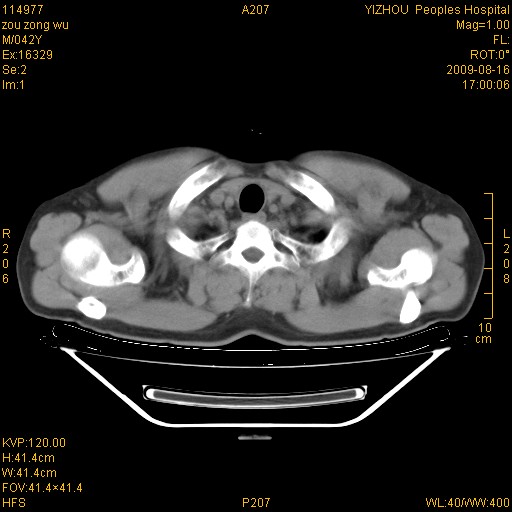

以下是引用zjzjr在2009-8-17 10:42:00的发言:[br]右侧间质性肺炎伴纤维化,右肺下叶肺囊肿伴感染(不除外外伤后引起),右肺野及胸壁软组织\\肝内见多发斑点状,中枪了吧.右侧胸膜肥厚\\粘连.